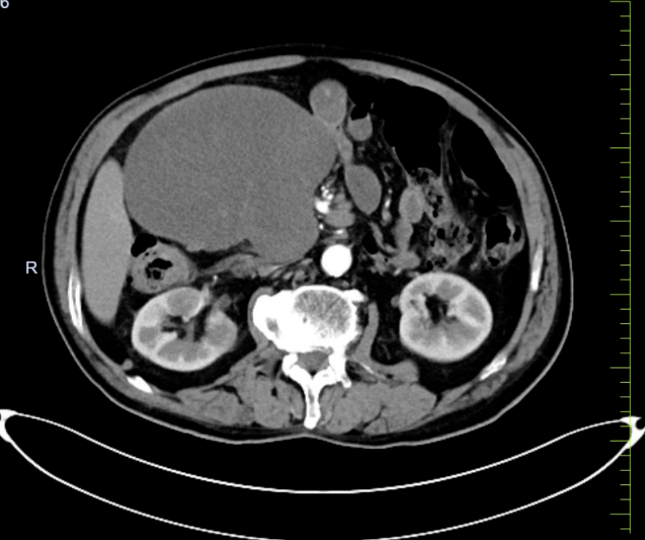

该患者因泌尿系结石于当地医院行CT检查时,发现右中上腹部肠系膜区域存在巨大占位。转入我院后,增强CT检查显示:上腹部肠系膜脂肪间隙内见巨大团块状稍低密度影,病变内可见小血管,且与周围肠管边界不清。尽管患者当时无明显不适症状,但影像学评估提示肿瘤血供极为丰富,并与肠系膜上动静脉关系密切,手术切除难度大,术中面临出血和肠坏死风险。